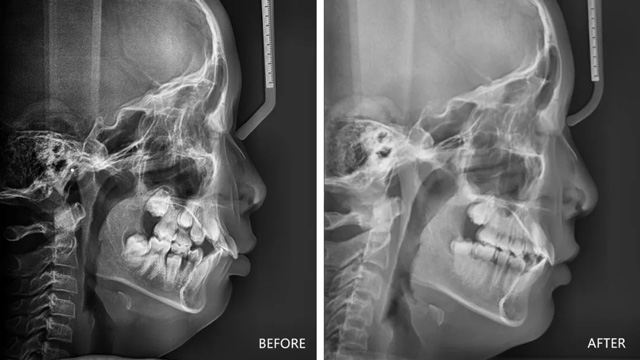

儿童下巴后缩治疗前后